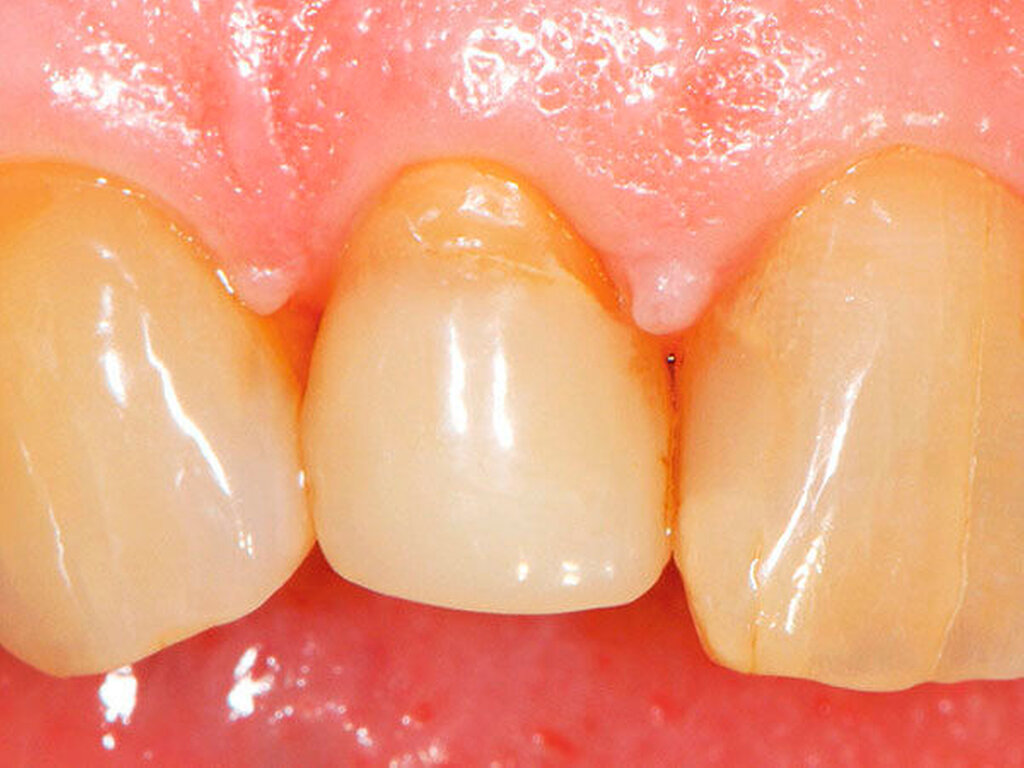

Am Beispiel von Abbildung 1 (stark zerstörte Zahnkrone eines Schneidezahns) kann das Prinzip der frugalen Intervention erläutert werden:

Durch die Erfolge der Adhäsiv- und Komposittechnik kann heute folgendermaßen vorgegangen werden:

Verzicht auf Wurzelkanalbehandlung / Erhaltung der Vitalität des Zahns

Verzicht auf Wurzelkanalstift

direkte minimalinvasive Kompositkrone (Verzicht auf indirekte Vorgehensweise)

Schonend: Die oralen Strukturen werden geschont und die Versorgung ist hinreichend stabil. Durch den Verzicht auf Wurzelkanalstifte wird das Wurzelfrakturrisiko reduziert. Zudem können Material-, Geräte- und Personalressourcen aus Praxis und Techniklabor, die beim klassischen Vorgehen anfielen, reduziert werden.

Gut genug: Ästhetische Feinheiten lassen sich bei direkten Restaurationen nicht immer in gleicher Perfektion einarbeiten wie bei indirekt gefertigten Kronen, auch die Stabilität des Hochglanzes lässt bei einigen Kompositpräparaten noch zu wünschen übrig. Andererseits erlauben die direkten Verfahren inzwischen mitunter sehr flexible Vorgehensweisen, die sich auch mit Farb- und Formkorrekturen von Zähnen kombinieren lassen. Die Erwartungen eines großen Teils der Patienten werden hinreichend erfüllt und die Nutzen-Risiko-Relationen wie auch die Aufwand-Kosten-Relationen erscheinen – wenn auch nicht durchgängig – so doch zumindest in vielen Fällen günstig.